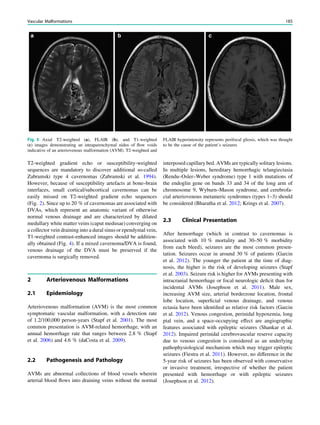

Fig. 2 Dural a. v. fistula. A 53-year-old man presented with two tonic–

clonic seizures. MRI shows circumscribed edema in the left frontal lobe

(a, hollow arrow) and an abnormal vessel running in the left sulcus

rectus (c, arrow). The digital subtraction angiogram of the left internal

carotid artery shows a frontobasal dural arteriovenous fistula fed via

ethmoidal arteries (d, arrow) and confirms the abnormal vessel as a

draining vein (e, arrow)